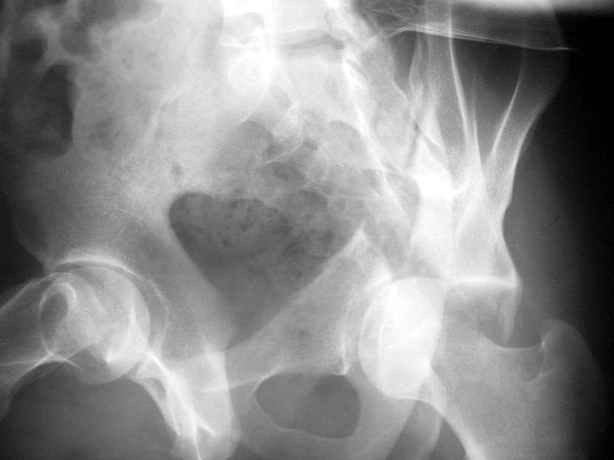

Уважаемые коллеги,Мужчина 36 лет от роду попал в ДТП 24.08.04 Рентгенограммы в приложении.

Диагноз- перелом с вовлечением таза, разрыв правого сакро-илиак сочленения vertical shear injury, перелом крыла подвздошной кости?, перелом ацетабулум Т type или Both column?, перелом шейки бедра, перелом проксимального отдела бедра.

перелом крыла правой подвздошной кости, перелом обеих колонн вертлужной впадины, двусторонний перелом лонных костей (С2.2) повреждение передних связок правого крестцово-подвздошного сочленения,

ипсилатеральный перелом шейки и диафиза бедра.